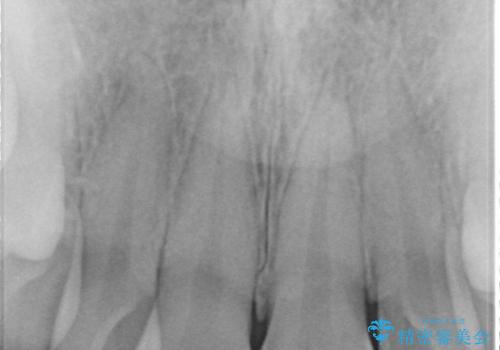

- 前歯の突出を主訴に来院。

矯正治療は絶対したくないとのことでした。

矯正治療をするメリット(神経を取らずに済む、歯を削らずに済む、セラミックを入れずに済む、歯ぐきのラインが整う)をお話しましたが、希望されませんでした。

部分矯正なども提示しましたが、早く治すセラミック治療を選択されました。

前歯の角度や歯ぐきのラインに差が大きかったため、やむなく神経をとり、歯ぐきの手術を行い出来るだけ歯ぐきのラインを整えるようにしました。

手術をしなければ左上1番の歯ぐきのラインは左上2番よりも下にきてしまい、長さの短い歯になってしまうところでした。

笑っても大きく歯ぐきが見える方ではなかったので、歯ぐきのラインが目立つことはなかったです。

手術をしなければ左上1番の歯頚ラインは左上2番よりも短い位置になっていたため、歯自体の長さが不自然なほど短くなってしまったと思います。